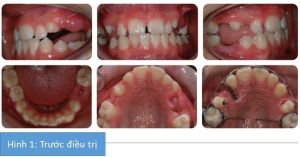

Bệnh nhân nam 14 tuổi có tương quan răng cửa hạng III trên nền xương hạng III nhẹ, phức tạp bởi:

- R13, R15, R25, R35 không mọc

- Nhóm răng phía trước hàm dưới chen chúc nhẹ

- R14 xoay.